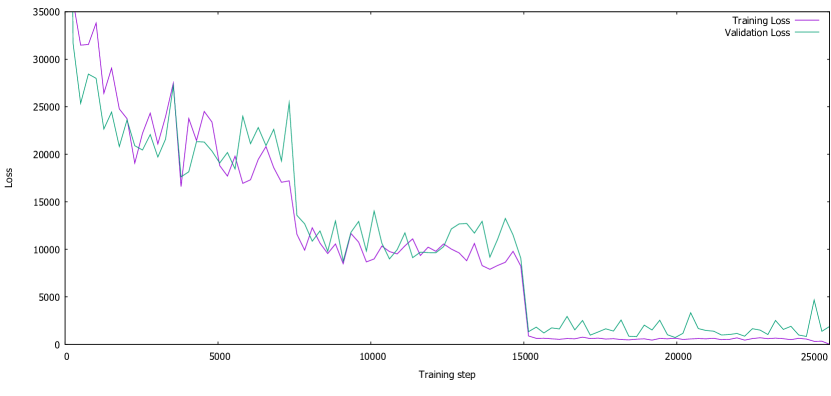

The training evolution is somewhat noisy but the network steadily converges, as seen in the graph presented in Figure 3.11.

For test on the LiTS challenge volumes, the lesion segmentation dice score is 0.586 while for the liver it reaches 0.938.